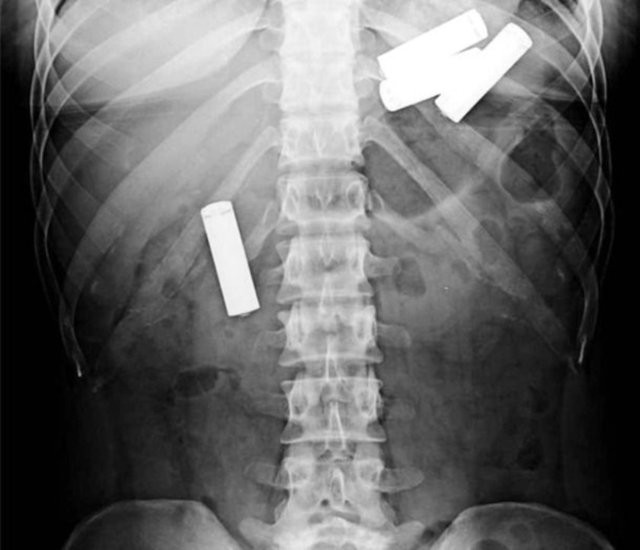

Piller